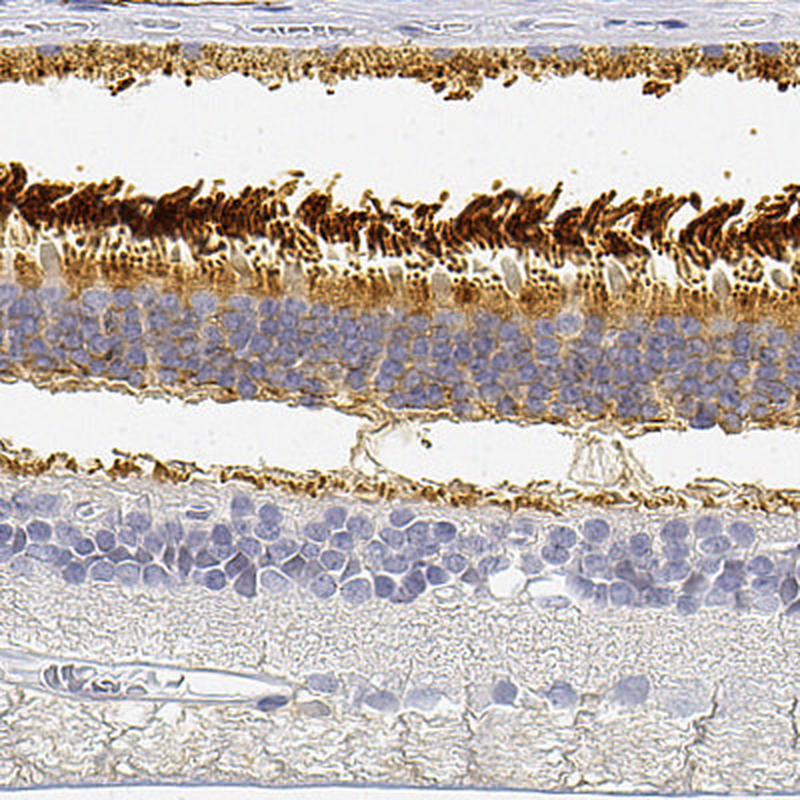

Immunohistochemical staining of human retina shows strong cytoplasmic positivity in photoreceptor cells and outer plexiform layer.